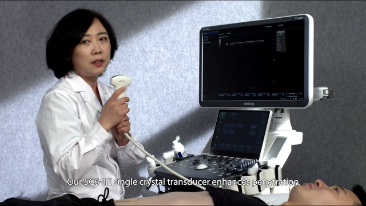

ImГЎgenes ClГӯnicas

Transductores